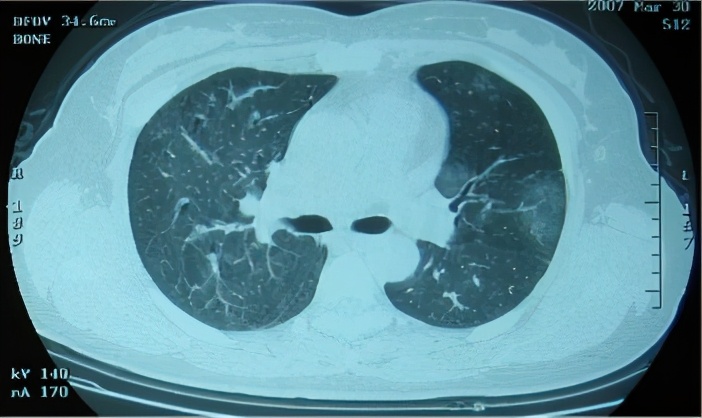

从影像学可以看到,有一些网格索条影,小叶中心型结节,很多气体分布不均,像马赛克征的情况。

急性和亚急性过敏性肺炎的胸部CT的差距就比较明显,我们可以看到典型改变:小叶中心结节,边界不清,弥漫分布;轻症患者CT也可无明显异常;磨玻璃样/实变,片状或弥散,支气管血管束,下叶分布;肺气肿或马赛克征象。

胸部CT:不规则索条影、网格、结节(小叶中心)、磨玻璃;肺结构改变更明显,支气管扩张,蜂窝肺;肺皱缩(上叶)下叶代偿性肺气肿,但是无钙化和空洞;马赛克(主要见于亚急性/慢性);支气管血管束增重。

2)CT特点: 马赛克/气体陷闭、磨玻璃、细小结节、蜂窝肺、纵膈淋巴结肿大等最常见。